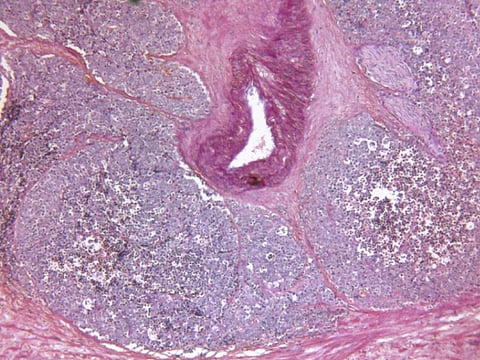

Sangeet Ghai, M.D., from the University of Toronto, and colleagues conducted a prospective phase II trial involving men with unifocal clinically significant prostate cancer visible at MRI who were treated with transrectal MRI-guided focused ultrasound between February 2016 and July 2019. MR thermography was used to perform real-time ablation monitoring. At treatment completion, nonperfused volume was measured.

The researchers found that all 44 men successfully completed treatment, including 36 and eight with grade group 2 and 3 disease, respectively. There were no major treatment-related adverse events reported. At five-month biopsy, 41 of the participants (93 percent) were free of clinically significant prostate cancer at the treatment site. At baseline and at five months, both median International Index of Erectile Function-15 (IIEF-15) and International Prostate Symptom Score measurements were similar. Compared with smaller ablations, larger ones (≥15 cm3) were associated with a reduction in IIEF-15 scores at six weeks.